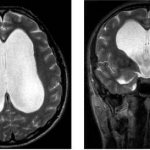

Ни одно из угрожающих жизни осложнений не может быть обнаружено иначе, чем с помощью рентгенографии или КТ. Состояние здоровья пострадавшего может резко ухудшиться в ближайшие дни.

Непосредственно после травмы нельзя положиться даже на рентгеновское изображение – отек на нем может не показываться. Тяжесть состояния может быть оценена только через несколько дней или даже недель.